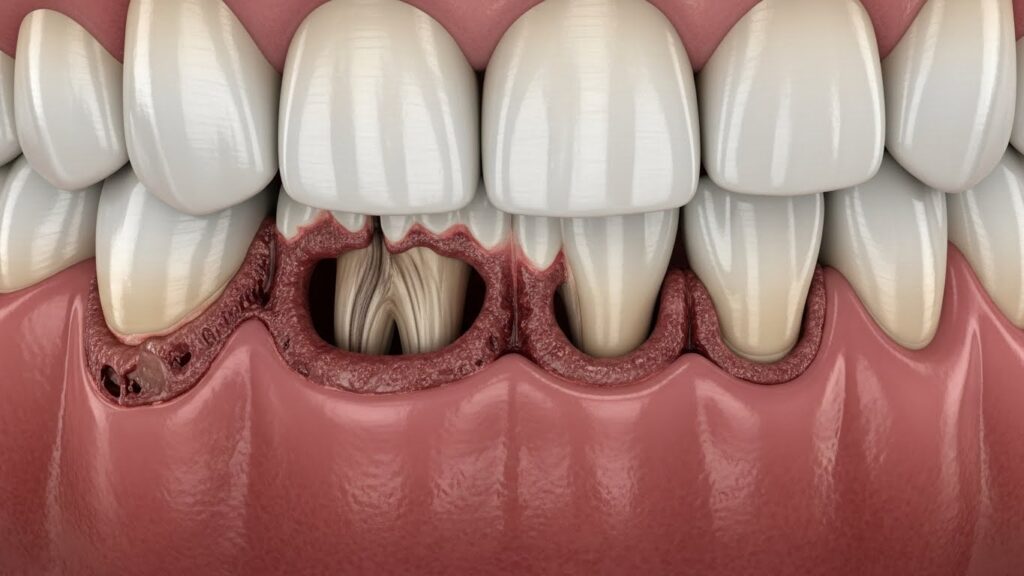

TISSUE BREAKDOWN

Gums slowly pull back, exposing roots, increasing sensitivity, and creating pockets where harmful bacteria thrive.

This is when most people finally realize something is wrong — but still don’t know the real cause.